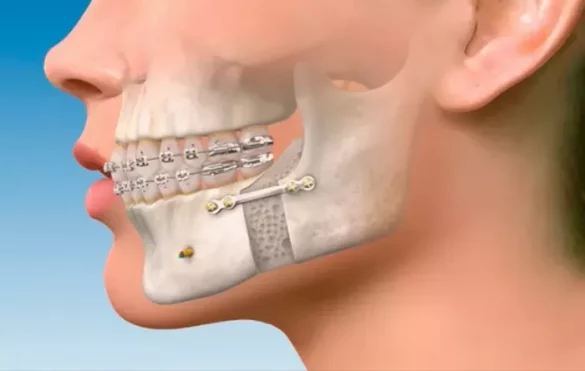

When jaw asymmetry is caused by differences in the size or shape of the jawbones themselves, braces alone usually cannot fix the problem. In these cases, the jawbones need to be repositioned surgically. This is called orthognathic surgery.

After surgery to correct the jaw position, braces are typically used to fine-tune the teeth alignment and bite. The combination of surgery and braces is often the most effective treatment for severe asymmetry.

Role of Orthodontics and Surgery Together

Many patients with jaw asymmetry need a combined approach. First, an orthodontist will place braces to align teeth before surgery. Then, a maxillofacial surgeon performs the jaw surgery to correct bone positions. Finally, braces continue post-surgery to perfect bite and alignment.

This teamwork ensures the best possible outcome for both function and appearance.